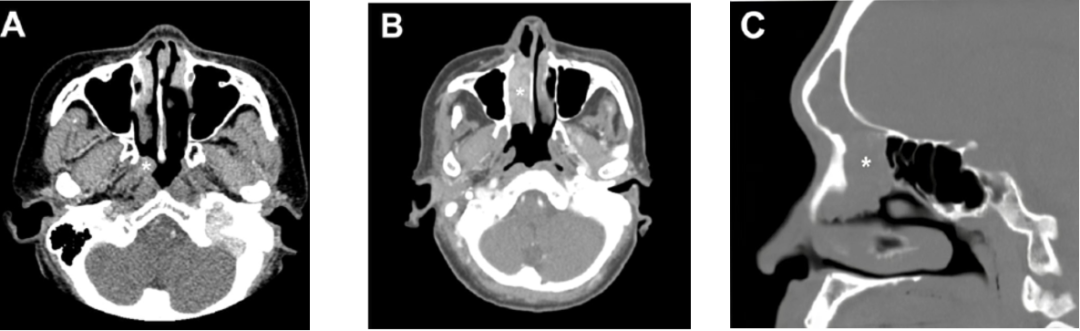

DEK-AFF2 癌是鼻腔鼻窦非角化性鳞状细胞癌的罕见亚型,2022 年 WHO 头颈部肿瘤分类纳入其中。好发于男性(男女比例 3:2),年龄 18~79 岁(中位 58 岁),多见于鼻咽、鼻腔和鼻窦等部位,泪囊发病罕见